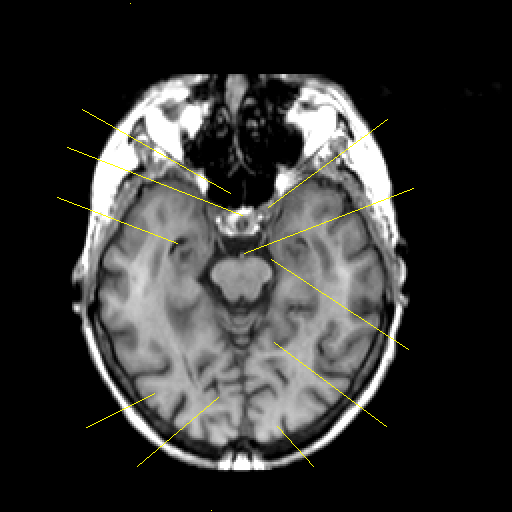

T1-weighted structural MR: Slice 20

Slice 20

Pointers

Labeled